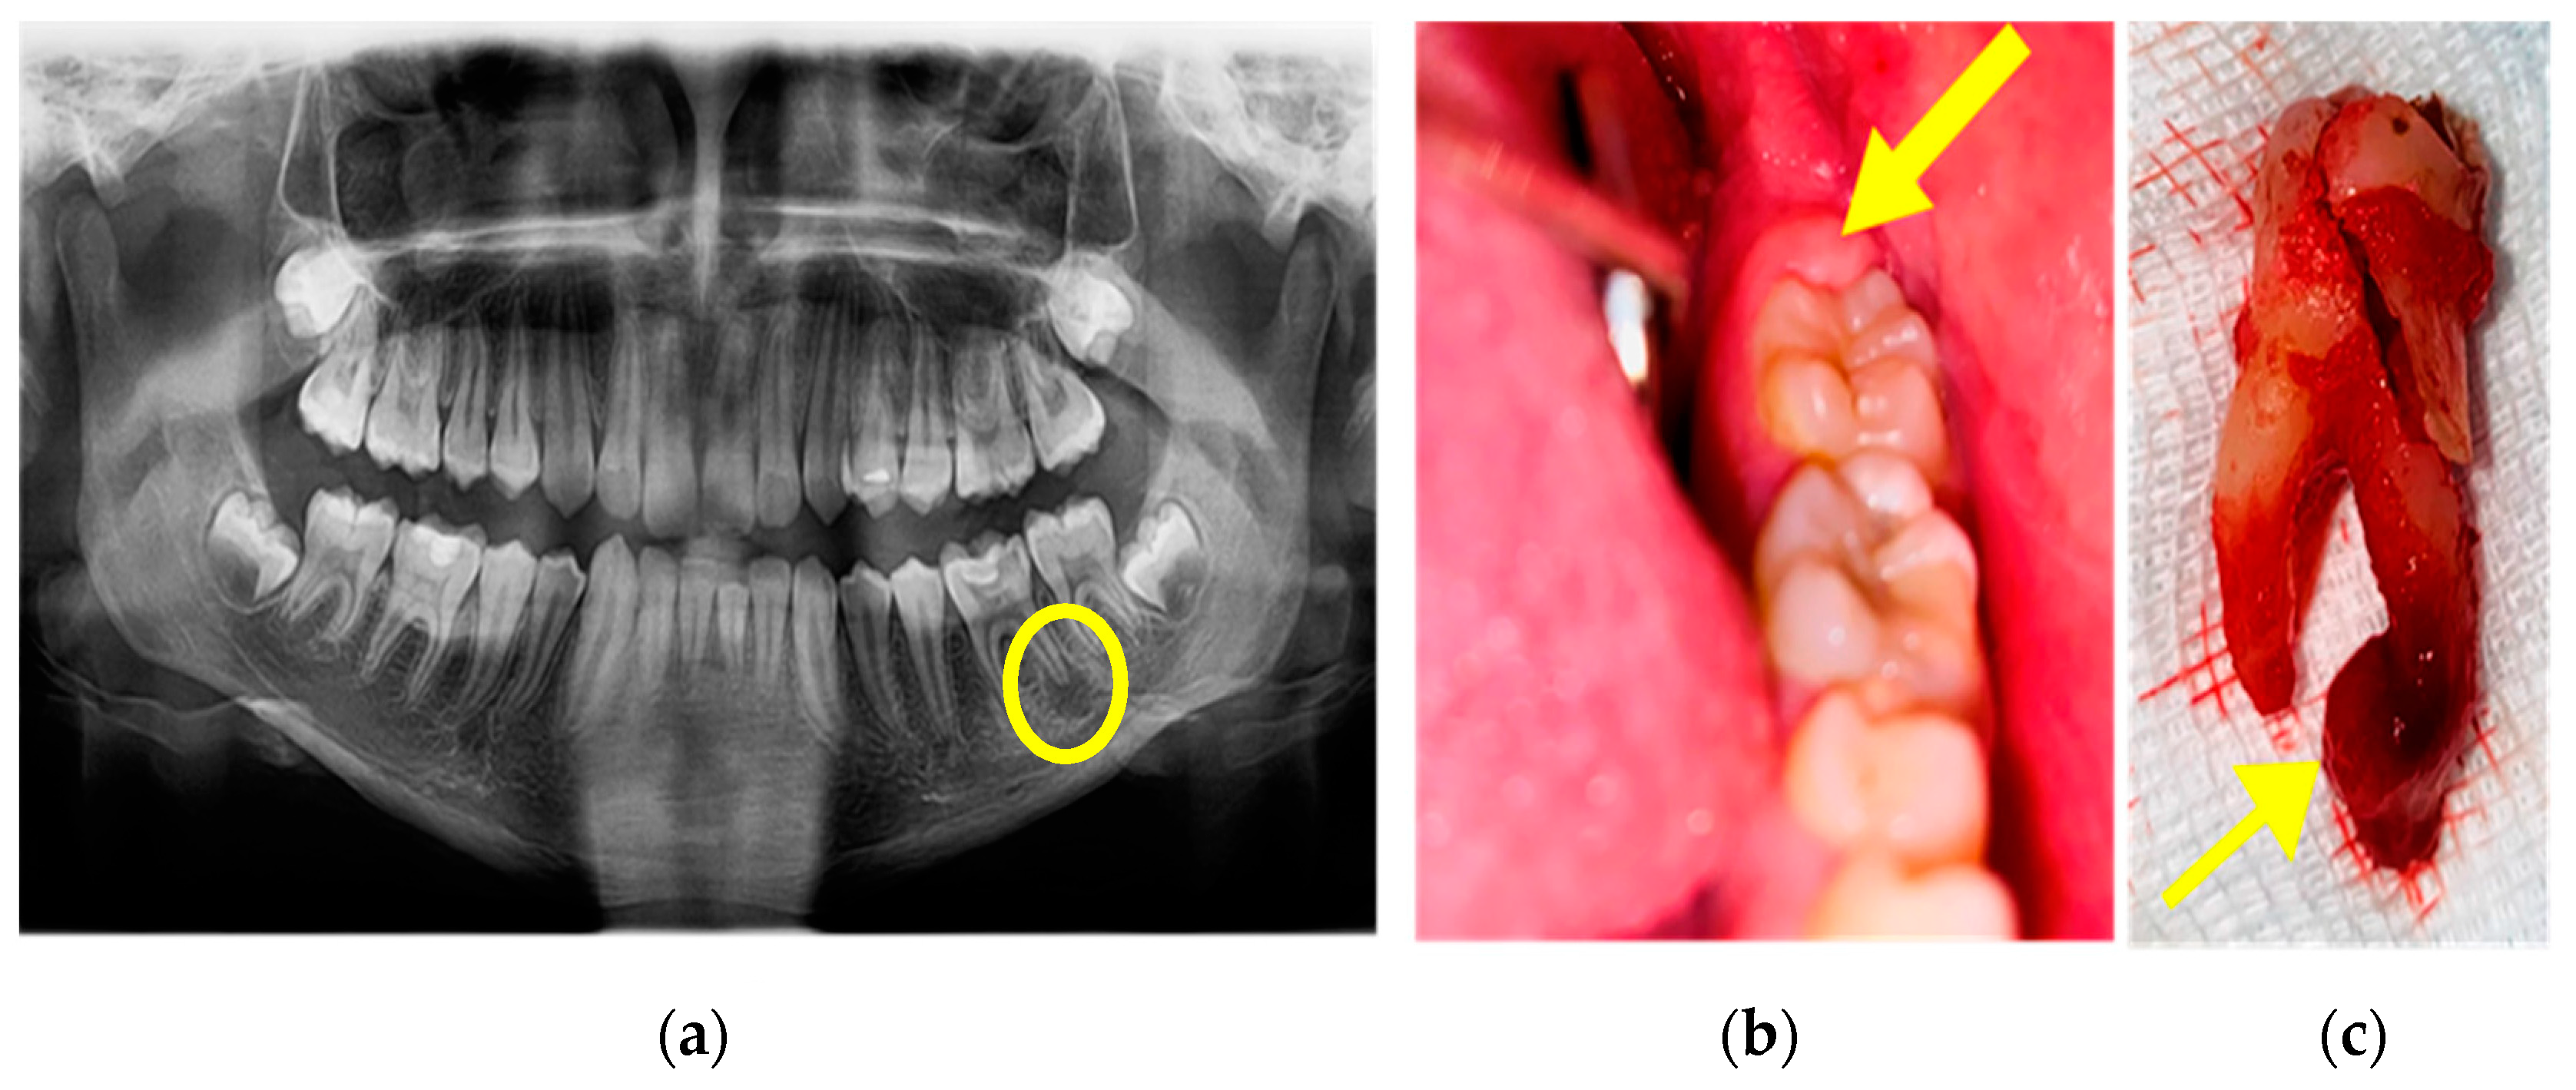

On 25th day in the ICU, bronchial lavages were performed (for 5 days), with the removal of blood clot formed in larger caliber bronchi (Figure 4).

Figure 4. Blood clot: (a) endoscopic view and (b) removal of the blood clot.